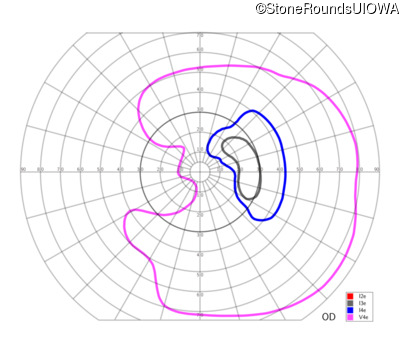

This 81 year old man began using a flashlight to read menus in his 40's. At age 75 his ophthalmologist noticed abnormal fundus findings and referred him to a retina specialist.

Diagnosis & molecular findings

| Late Onset Retinal Dystrophy | C1QTNF5 | Ser163Arg AGC>AGA | AD |